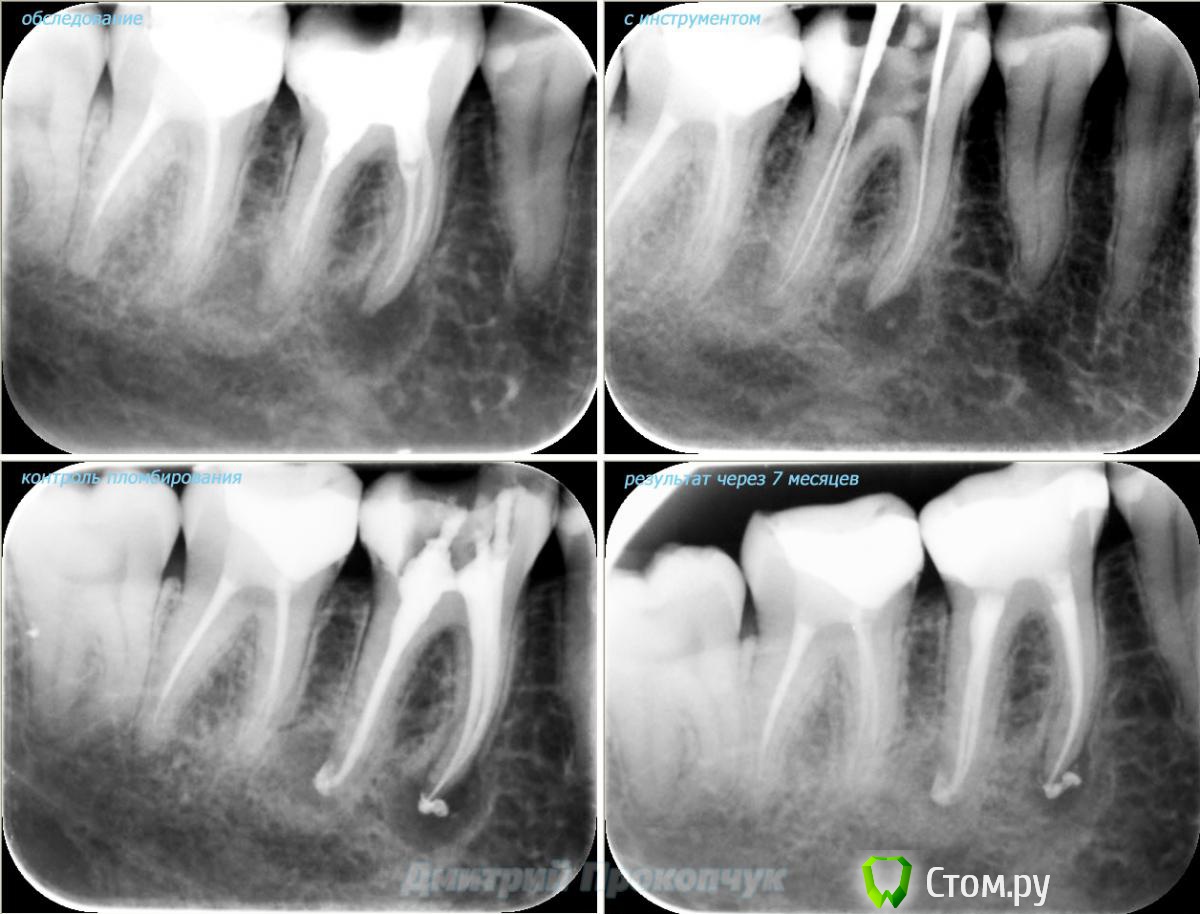

punkrat Опубликовано 16 сентября, 2014 Поделиться Опубликовано 16 сентября, 2014 Коллеги, тема , возможно, не имеет смысла просто приятная мне эндодонтия, сохранил с предыдущего места работы. Да, будь я проклят, я все знаю, НИГДЕ НЕТ КОФЕРА, на новом месте с этим норм. В общем если посчитаете, что я недостоин постить тут свои снимки, то так тому и быть, удалю тему.. 01. плановый ретрит 46ого и результат через 7 месяцев. Осложняющим моментом тут было то, что длина каналов была около 26 мм... 02. первичное эндо 34 (подготовка к ортопедии) + бонус - ретрит 35 03. ретрит 26 (подготовка к ортопедии) 04. ретрит 15, 16 (подготовка к ортопедии). основная сложность была в ретрите 15 - он был запломбирован термафилами, да еще снабжен свш... 05. ретрит 27 (подготовка к ортопедии). Ничего особенного, со временем посмотрим какова будет убыль этого совсем немаленького разрежения 06. ретрит 13. Разумеется пришлось выбивать вкладку, а потом еще попилить 3-4 миллиметра цемента, но, таки попилил куда нужно... 07. ретрит 17 (подготовка к ортопедии). В данном случае я, кажется, потратил больше времени на снятие литого моста, чем на лечение 17)) 08. ретрит 16 (подготовка к ортопедии). Снимка с инструментом нету, поскольку, визиограф сломался и его делал на пленку. 15 разумеется тоже перелечен... 09. плановый ретрит 16 10. первичное эндо 36, рядовой случай что дистальный щечный удалось найти не сразу, он был спрятан под нависающим дентиклем 11. ретрит 12, 11 (подготовка к ортопедии). Казалось бы, рядовой случай, если бы корневые каналы обоих зубов не были бы налухо забиты резорцин-формалиновой смесью... 12. ребенок 9ти лет, острый пульпит 46, попробовал оставить витальным. Пока полет нормальный, но даже если придется делать эндо в последствии, лучше когда оно будет сделано в более старшем возрасте... 13 Ссылка на комментарий